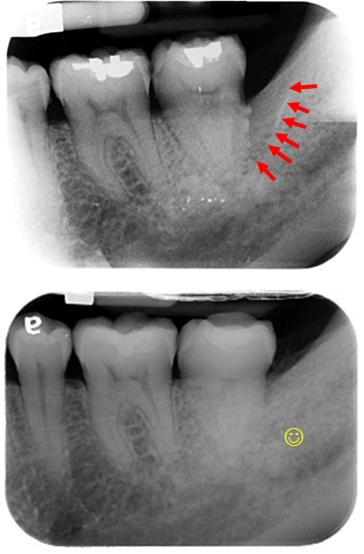

醫師診斷及治療前

患者常抱怨早期拔完智齒後前一顆牙齒的牙肉反覆腫脹,經檢查發現......

發現左右邊的第二大臼齒 骨頭缺損嚴重

左側

右側